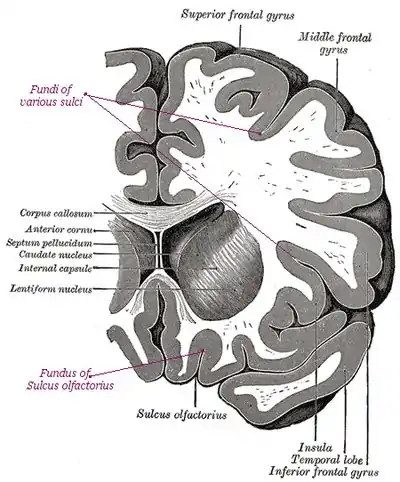

A gyrus is an outward folding of the brain, for example the precentral gyrus. A sulcus is an inward fold, or valley in the brain's surface - for example the central sulcus. Additional terms used to describe these may include:

- Annectent gyrus, for a small gyrus hidden in the depth of a sulcus

- sulcal fundus, for the bottom of a sulcus, an inward fold